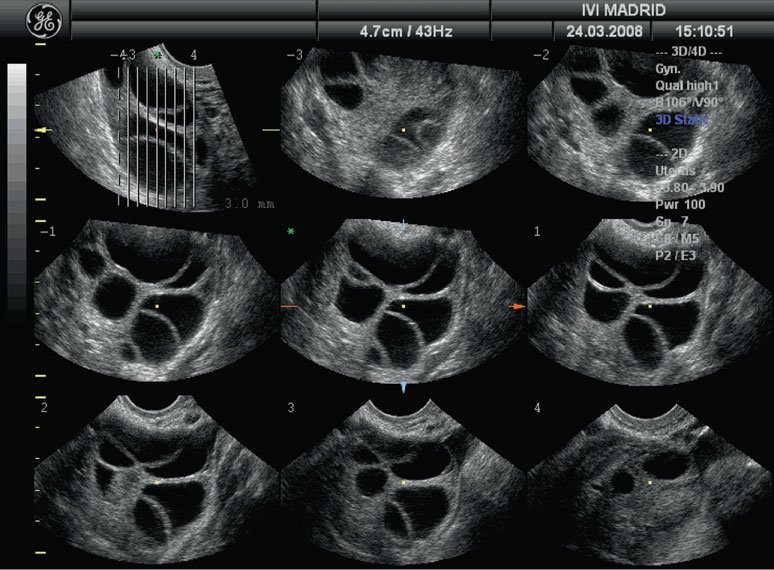

4. 3D Pelvic Ultrasound:

Advanced imaging provides three-dimensional visualization for accurate diagnosis of uterine or ovarian conditions.